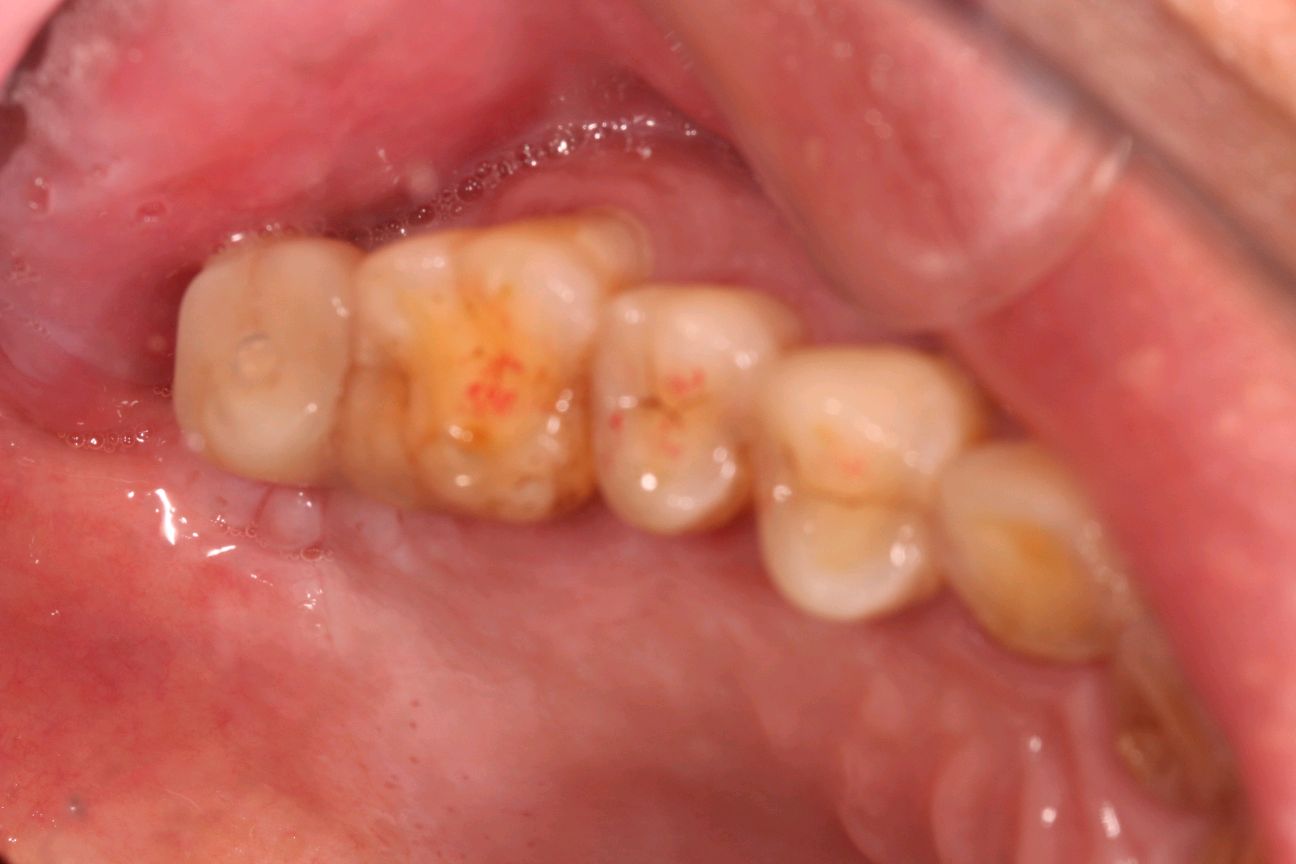

患者是成功人士,平时非常忙碌,忽略了口腔健康,直到有一天无法咀嚼食物后才想到要治疗牙齿,我们为他摄了CBCT,发现有重度牙周病,上合双侧7自然脱落,左上8,III度松动,并近中倾斜移位,对合牙严重伸长,还有其他牙齿疾患,需要综合治疗;经过牙周病治疗、上合窦骨增量、上合种植修复、拔牙、截冠、根管治疗、桩冠、高嵌体修复等!时间长达一年,终于恢复了正常牙列!可以享受食物的美好!